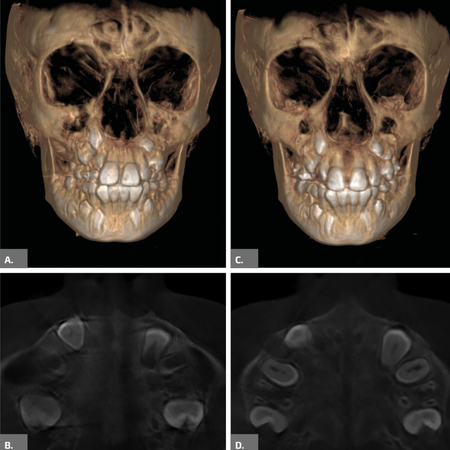

Maxillary second molar intrusion with  skeletal anchorage

INTRODUCTION: Skeletal anchorage enables targeted interventions for pre-prosthetic corrections, whether for dental crowns or implants. Patients with limited bone structure or contraindications for prior orthodontic treatment may present limitations in using skeletal anchorage. OBJECTIVE: To present a clinical case report involving the intrusion of an upper second molar to correct the interocclusal space, enabling the rehabilitation of its antagonist. This is a case with a quick and effective...